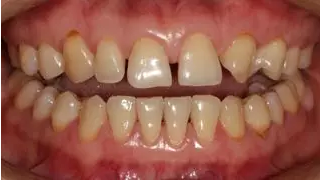

術前全牙弓非咬合照

病例分享|復合樹脂微創(chuàng)美學修復關閉上前牙間隙

術前上前牙正面照